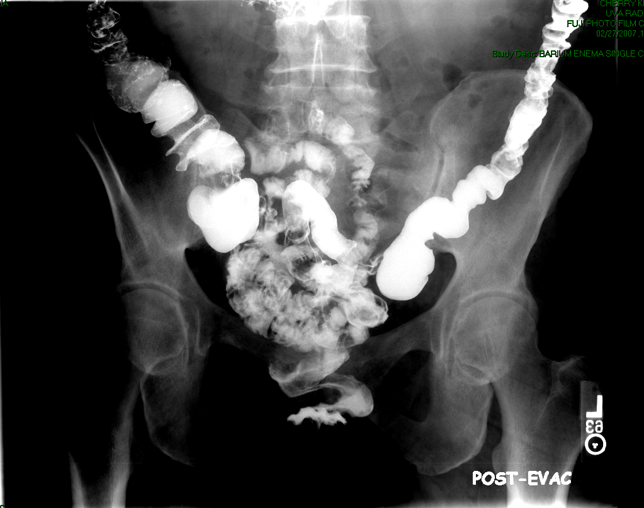

- Once you have obtained spot images of the entire colon, the technologist will then obtain the post study overhead radiographs:

- AP or PA position to include the entire colon. PA is preferable if the patient can tolerate (it may be necessary to take more than one image to image the whole colon)

(key image 12)

(key image 13).

- When the patient has finished using the restroom, the technologist will obtain a post evacuation overhead radiograph

(key image 18)

(key image 19).